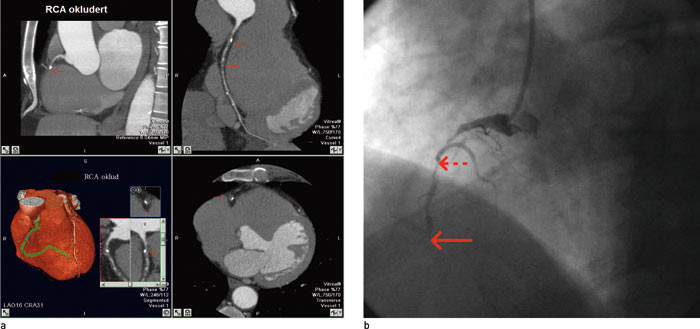

Okklusjoner viste seg å kunne være et diagnostisk problem med CT-angiografi. Retrograd fylling førte til relativ god fremstilling av karet distalt for okklusjonen, og man kunne derfor risikere underestimering av en kort proksimal okklusjon (fig 2).